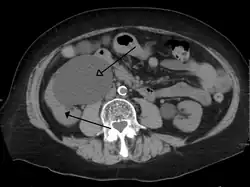

CT scan of bilateral hydronephrosis due to a bladder cancer -